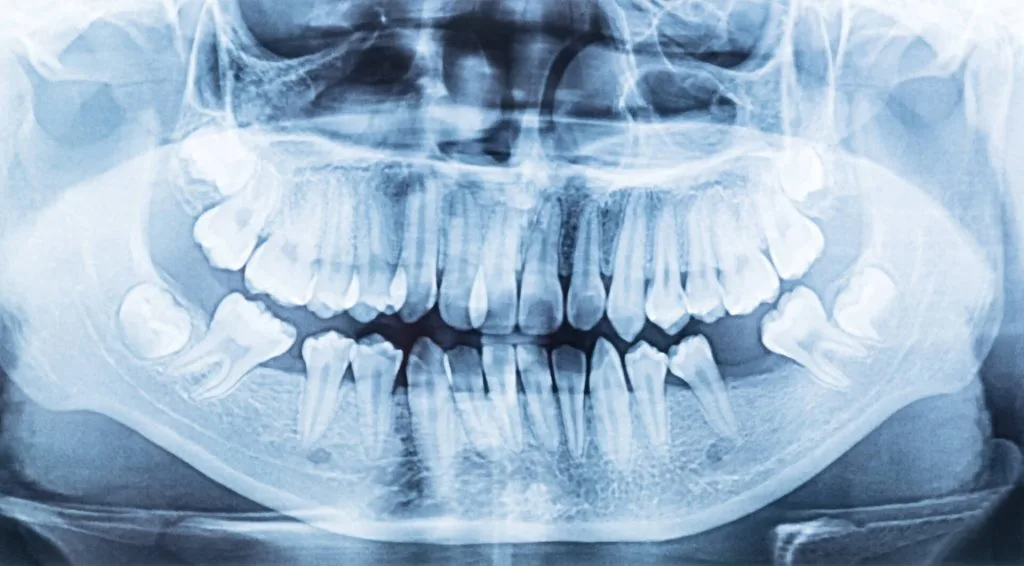

Tomografia CBCT 3D tworzy trójwymiarowy model uzębienia, kości, stawów i zatok. Lekarz ogląda każdą strukturę z dowolnej strony i w dowolnym przekroju – bez nakładania tkanek na siebie jak na zwykłej panoramie OPG. To nie jest lepsza wersja RTG – to inny wymiar informacji.

Relacje kątowe i liniowe między szczękami na modelu 3D. Pozycja korzeni w kości. Asymetria twarzy mierzona precyzyjnie – podstawa planowania leczenia ortodontyczno-chirurgicznego.

Rozległa rekonstrukcja obu łuków

Obie szczęki w jednym skanowaniu – mapa kości we wszystkich kwadrantach. Właściwe przy implantacji wielomiejscowej, obustronnym podniesieniu dna zatoki i rekonstrukcji All-on-4/6.

Tomografia CBCT szczęki i żuchwy

Obie szczęki w jednym skanowaniu – obustronna ocena zatok i kanałów żuchwowych. Jeden plik dla ortodonty, implantologa i chirurga.